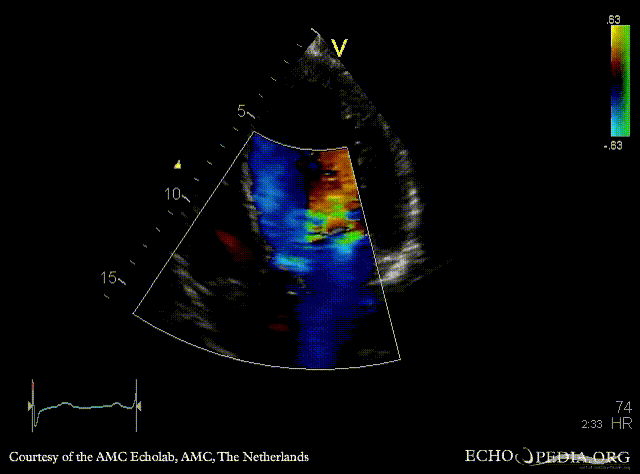

E00446.gif E00447.gif

A5CH A5CH: Color Doppler, severe aortic regurgitation